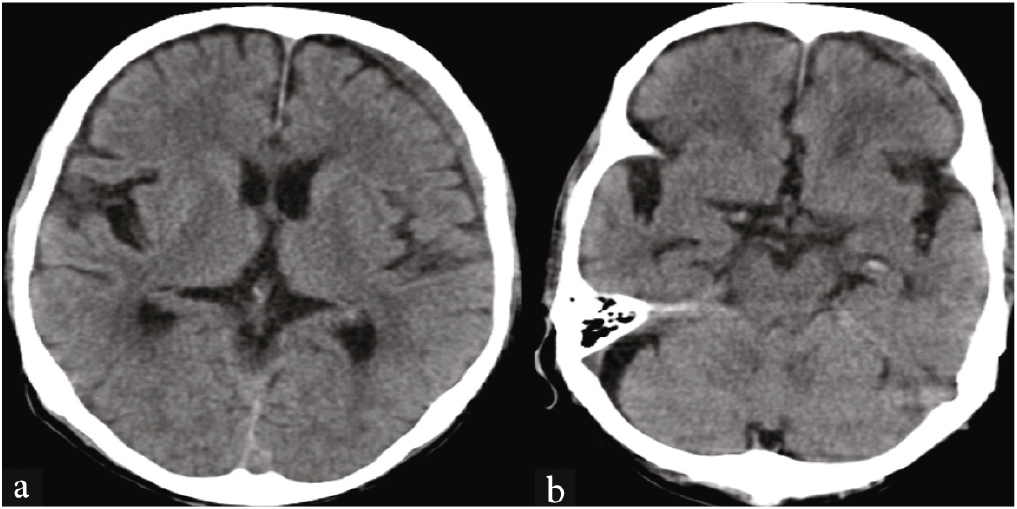

CT brain showed a subacute subdural hemorrhage in the left cerebral convexity [Figure 4a], along with lacunar infarcts in the midbrain and pons [Figure 4b]. The patient was diagnosed with left subacute subdural hematoma, which was referred for neurosurgical management. This case underscores the importance of considering subdural hematoma in elderly patients presenting with acute psychiatric symptoms, especially when there is no clear history of trauma.

- CT brain: (a) Subdural hemorrhage in the left cerebral convexity, (b) lacunar infarcts in the midbrain and pons.